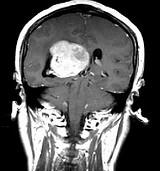

问题 女,45岁,右眼视力下降8个月,右颜面麻木半个月,时有头昏,味觉减退,请根据所提供图像,选择最可能的诊断()

选项 A.(右侧脑室)脑膜瘤(合体细胞型) B.(右侧脑室)室管膜瘤 C.(右侧脑室)脉络膜乳头状瘤 D.(右侧脑室)胶质瘤 E.(右侧脑室)转移瘤

答案 A